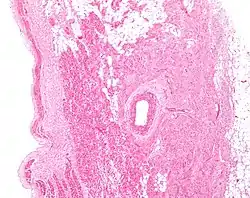

![]() Low magnification micrograph of a sinoatrial node (central on image), surrounding the sinuatrial nodal artery (on lumen in the image). H&E stain. | |

The sinoatrial node surrounds the sinoatrial artery, which can run centrally (in 70% of individuals) or off-center within the node.[4]